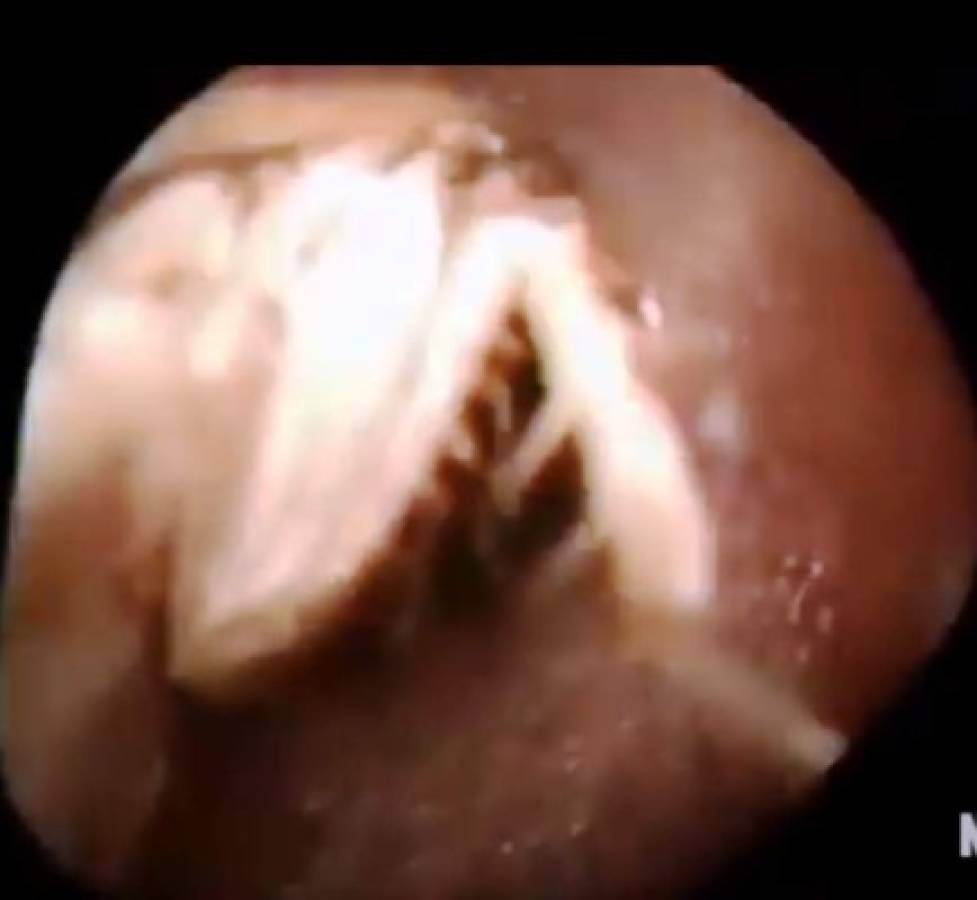

Al realizarle una exploración en el oído, los médicos encontraron algo impactante: Decenas de insectos bloqueaban el canal auditivo por completo.

Yang Jing, médico del Hospital Chang'an Xiaobian en la región del sur de China de la provincia de Guangdong, informó que tras hacer el inaudito descubrimiento procedieron a la extracción de aquellos bichos.

Al terminar, habían retirado 25 cucarachas bebés y una cucaracha hembra adulta.